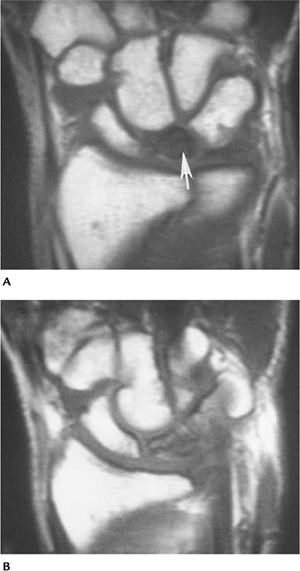

AVN can involve any osseous structure in

Kienböck disease is considered traumatic.

Routine radiographs often are normal in

MRI of AVN can be performed using T1- and

FIGURE 9-50 AVN of the lunate. (A) Initial T1-weighted MR image showing no signal (arrow) in the lunate because of AVN. (B)

Follow-up T1-weighted image after 3 months of cast immobilization showing return of signal to near normal after revascularization. |